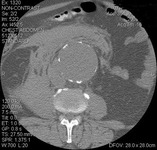

Aneurisma da aorta abdominal: tomografia computadorizada (TC) de um aneurisma da aorta abdominal roto

University of Michigan, mais especificamente os casos do Dr. Upchurch, representando os Departamentos de Cirurgia vascular e Radiologia